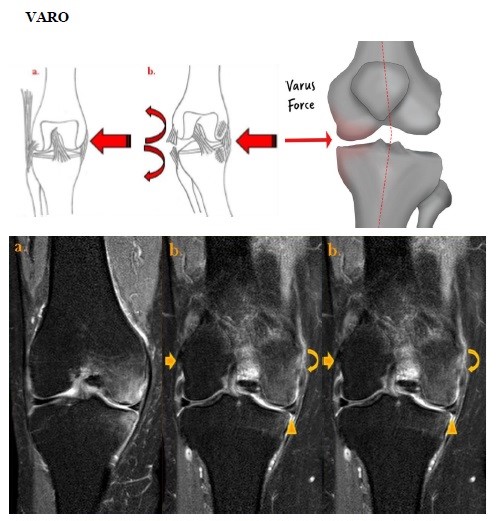

Varo

El trauma aislado en varo es un mecanismo lesional poco frecuente, ya que comúnmente lo vemos asociado a diferentes grados de flexión o extensión de la articulación. Está caracterizado por un patrón de contragolpe en el sitio de impacto y lesiones ligamentosas por distracción en el lado contralateral.

Patrones de edema óseo:

- Contusiones en la vertiente medial de la tibia y/o vertiente medial de cóndilos femorales.

Lesiones de partes blandas:

- Desgarros del ligamento colateral lateral y/o banda iliotibial.

Por lo que en general la vemos asociada a flexión y rotación interna de la tibia, donde comúnmente se ven afectados los componentes del cuadrante anterolateral, en especial las fibras posteriores de la banda iliotibial, dando como resultado una inestabilidad anterolateral. Este tipo de lesiones suelen presentarse en un individuo en movimiento, cuando el pie queda “bloqueado” al suelo con cierto grado de rotación medial originando por consiguiente la rotación interna de la tibia y la angulación en varo de la rodilla. En estas situaciones se pueden observar los siguientes hallazgos:

- Contusiones en el cóndilo femoral externo y esquina tibial posterolateral por impactación, secundario a la rotura del ligamento cruzado anterior.

- Edema secundario a fractura-avulsión de la inserción tibial de la cápsula articular lateral (fractura de Segond) o fractura-avulsión de la cabeza del peroné.

- Rotura del ligamento cruzado anterior y banda iliotibial.

- Mayor riesgo de lesión del menisco externo o interno y de la estructuras ligamentosas y tendinosas de la esquina posterolateral.[xxvii]

Lesión en varo

Dibujo que muestra la secuencia del traumatismo directo sobre la cara interna de la rodilla. (a) Articulación de la rodilla en posición neutra previo al trauma. (b) Posterior al traumatismo. Impactación de la superficie medial del cóndilo femoral interno. y del platillo tibial con las contusiones correspondientes en el sitio de impacto, además de distracciones severas en las estructuras laterales de la articulación, dando como resultado el desgarro del ligamento colateral lateral.

Imágenes coronales de secuencia potenciada en T2 con saturación grasa de la rodilla derecha en paciente con lesión por traumatismo en varo. (a, b) Edema óseo en la superficie medial del cóndilo femoral interno y del platillo tibial por impactación. (b, c) Esguince grado II del ligamento colateral lateral por distracción (flecha) y del ligamento colateral interno probablemente por trauma directo (flecha curva). Rotura oblicua de la unión cuerno posterior / cuerpo del menisco interno (cabeza de flecha).

Fuente: https://epos.myesr.org/posterimage/esr/seram2014/124014/mediagallery/577092